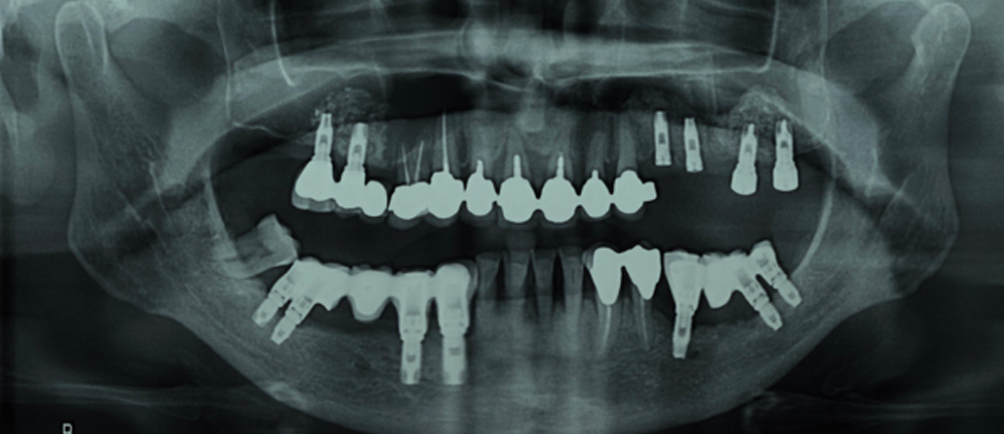

- Nel giugno 2004 diagnosi di Ca squamoso guancia sinistra.

- Nel gennaio 2005 Ca squamoso gengiva sinistra.

- Nel 2007 recidiva gengiva sinistra.

Buccofaringectomia con asportazione di tassello emimandibola sx piu’ linfoadenectomia (pT4 pN0) in associazione con radioterapia.